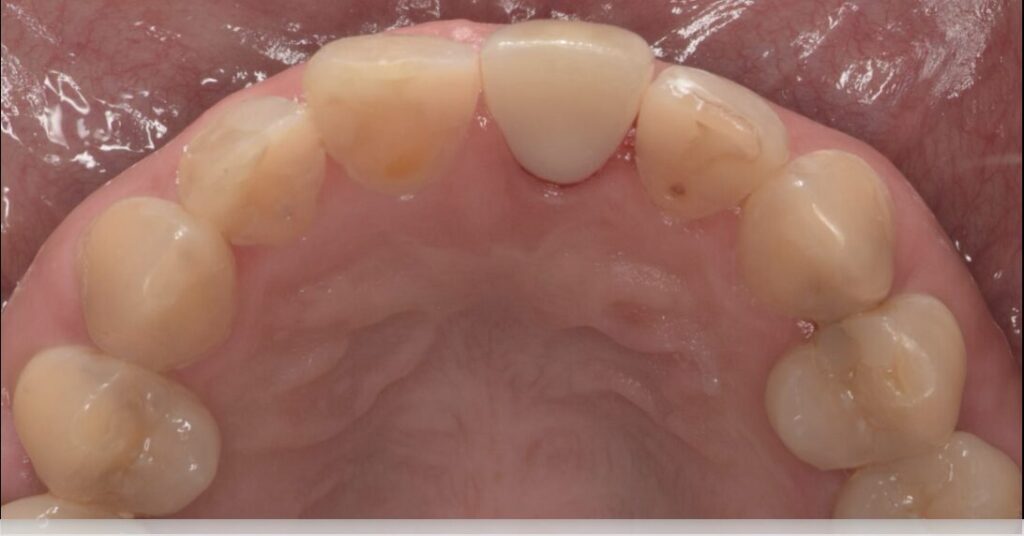

形成後